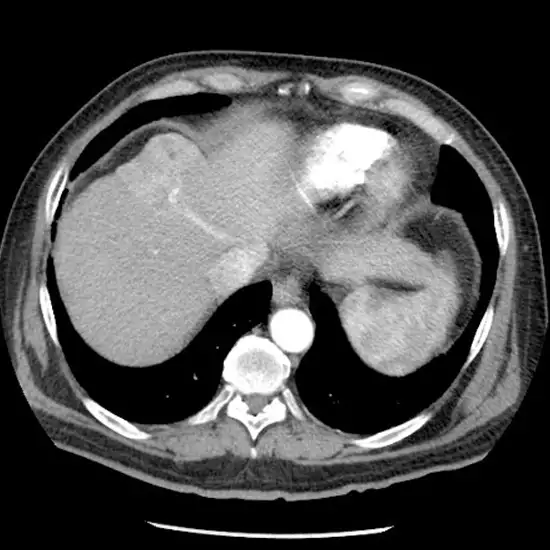

MRI Abdomen Triple Phase test consists of three phases. The first phase of imaging is done without contrast, the second is after injecting the contrast material into arteries and the third (the last one) is when the dye is flushed out of the portal veins.

The triple-phase MRI test is done to obtain detailed images to diagnose certain liver diseases, and vascular abnormalities and for evaluating organs. The images produced show detailed images of the abdomen, arterial, and portal veins that help in the diagnosis of liver diseases, and vascular conditions.

The MRI triple-phase test can help in differentiating abnormal tissues from normal tissues. It helps in determining conditions related to various organs of the body such as the liver, spleen, gallbladder, pancreas, etc.

As the name itself suggests, the MRI triple-phase test consists of three stages

Stage 1- This is the stage where an MRI scan is done without the use of a contrast medium.

Stage 2- In the second stage, contrast is injected into the arteries and then it is recorded

Stage 3- In this stage, the scan is recorded when the dye is flushed out of the portal vein.